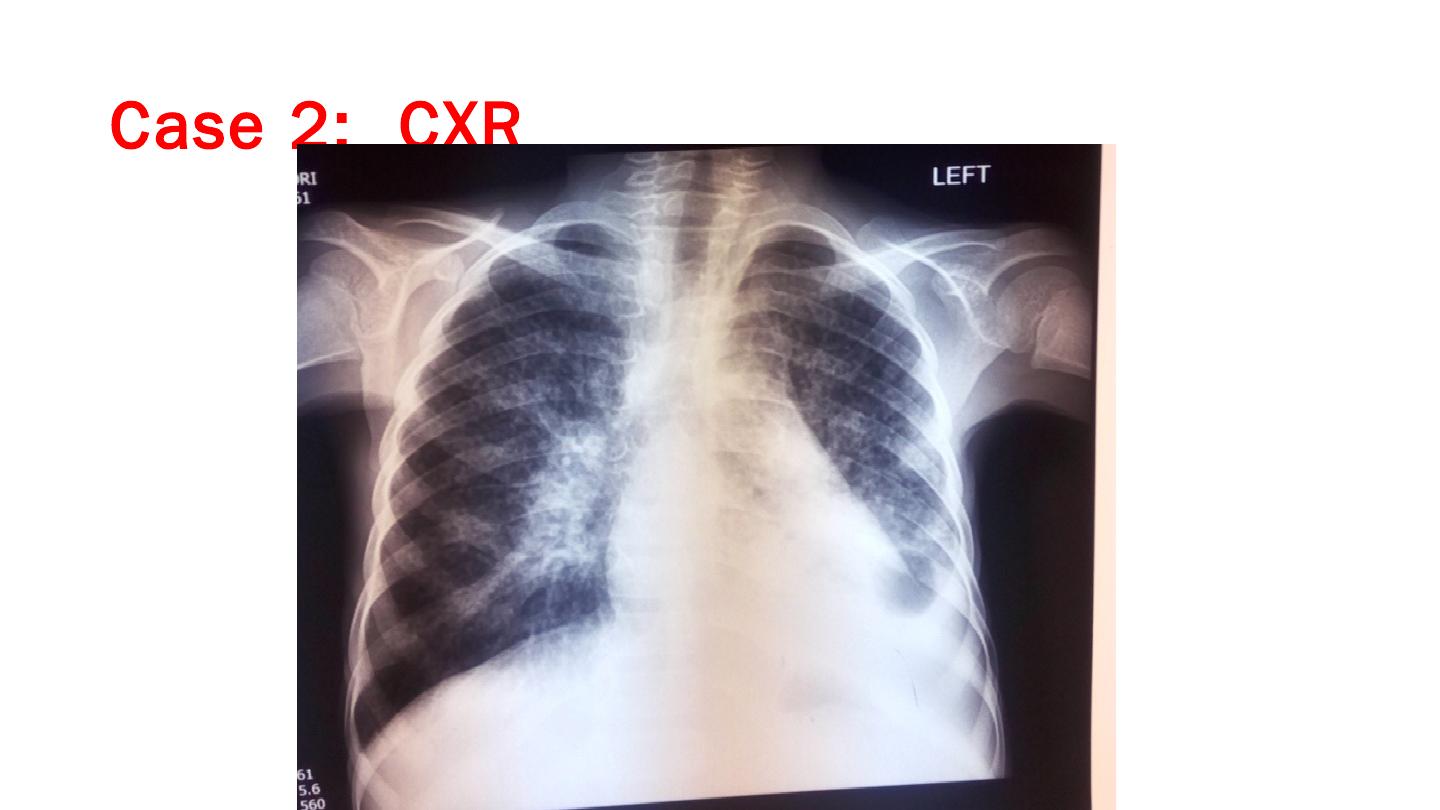

... on ABC;3TC;LPV/r); Her LNMP was 2/Feb/2015; The father of her daughter had asked them to leave; she in a new relationship with a 36 years old fisherman; ...